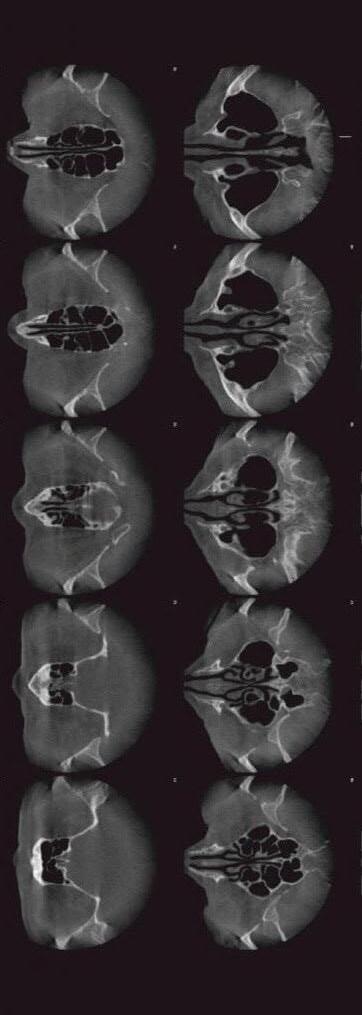

До об’єктивних методів дослідження відносять: -отоакустичну емісію -КСВП

-тимпанометрію.

Розглянемо ці медичні методи дослідження, що є більш фаховими у своєму використанні:

• Отоакустична емісія (ОАЕ)

– дозволяє дуже швидко та ефективнооцінитистанслуху

у малюка. При цьому слабкі звуки, котрі виникають внаслідок функціонування зовнішніх волоскових клітин, які зі свого боку сприяють посиленню коливання базилярної мембрани, а фіксація «відклику» та його характеристик взята за основу методу. Без нормального слуху дітки не можуть правильно формувати мову. Тому ті, хто народжується з приглухуватістю, потребують коригувальних заходів.Нажаль,цяпроблема єдійсновагомою,аджезастатистикою порушення слуху в новонароджених зустрічається частіше, ніж синдром Дауна та «заяча губа». Зі ста дітей близько шести народжуються

з «поганим» слухом.

•КСВП(коротколатентніслу-

хові викликані потенціали)

– є цілком безболісним та

нешкідливим для пацієнта

методом, що дозволяє виявити місця ураження слу-

хової системи у дітей та дорослих. Вагомо, що КСВП є найбільш надійним об’єктивнимметодомоцінкизни-

ження гостроти слуху в немовлят та дітей молодшого віку.

• Тимпанометрія або акустичної імпедансометрією – є ультразвуковим обстеженням середнього вуха, переважно слухової труби. Метоютимпанометріїєоцін-

ка стану пошкодження чи цілісності барабанної перетинки та слухових кісточок.

В основу методу покладено

використання звукового тиску з певною частотою та інтенсивністю у вусі.